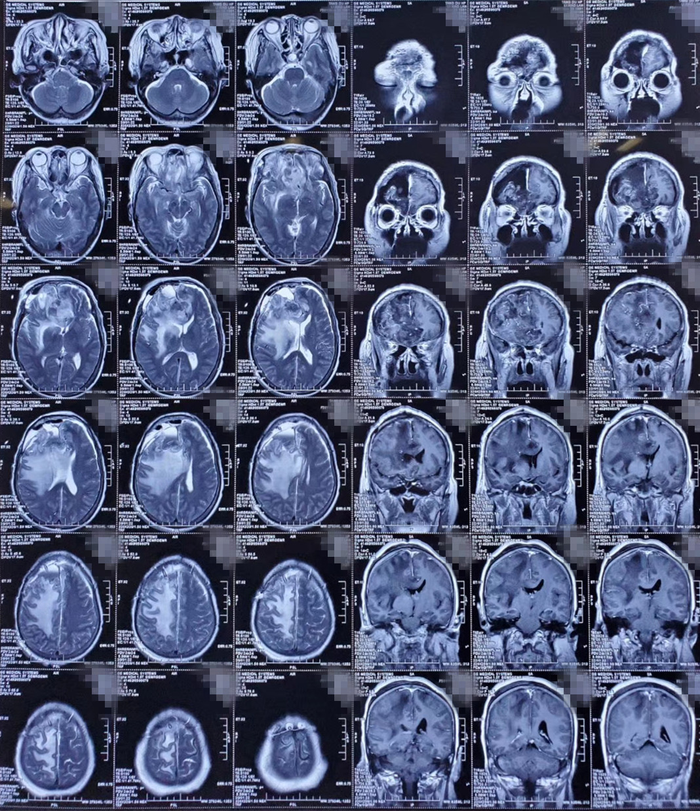

形形色色脑膜瘤

图片尺寸3530x3998